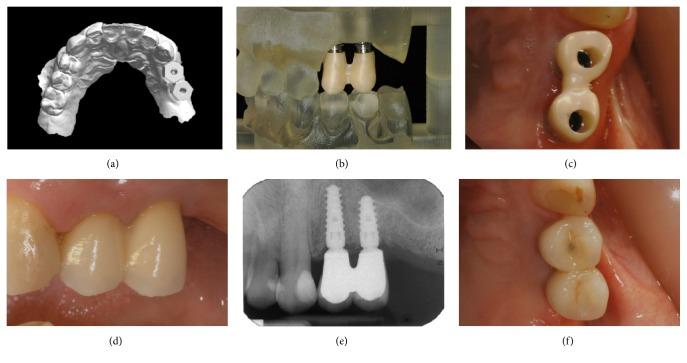

Scope. To demonstrate guided implant placement and the application of fixed, implant-supported prosthetic restorations with a fully digital workflow. Methods. Over a 2-year period, all patients with partial edentulism of the posterior maxilla, in need of fixed implant-supported prostheses, were considered for inclusion in this study. The protocol required intraoral scanning and cone beam computed tomography (CBCT), the superimposition of dental-gingival information on bone anatomy, surgical planning, 3D-printed teeth-supported surgical templates, and modelling and milling of polymethylmethacrylate (PMMA) temporaries for immediate loading. After 3 months, final optical impression was taken and milled zirconia frameworks and 3D-printed models were fabricated. The frameworks were veneered with ceramic and delivered to the patients. Results. Fifteen patients were selected for this study. The surgical templates were stable. Thirty implants were placed (BTK Safe®, BTK, Vicenza, Italy) and immediately loaded with PMMA temporaries. After 3 months, the temporaries were replaced by the final restorations in zirconia-ceramic, fabricated with a fully digital process. At 6 months, none of the patients reported any biological or functional problems with the implant-supported prostheses. Conclusions. The present procedure for fully digital planning of implants and short-span fixed implant-supported restorations has been shown to be reliable. Further studies are needed to validate these results.

范围。展示使用全数字工作流程进行引导式种植体植入以及固定的、种植体支持的修复体的应用。方法。在两年时间里,所有上颌后牙部分牙列缺失且需要固定种植体支持修复体的患者均被纳入本研究。该方案要求进行口内扫描和锥形束计算机断层扫描(CBCT),将牙齿 - 牙龈信息叠加在骨解剖结构上,进行手术规划,制作3D打印的牙齿支持的手术模板,以及为即刻负重制作和铣削聚甲基丙烯酸甲酯(PMMA)临时修复体。3个月后,获取最终光学印模并制作铣削氧化锆框架和3D打印模型。框架用陶瓷贴面并交付给患者。结果。15名患者被选入本研究。手术模板稳定。植入了30颗种植体(BTK Safe®,BTK,意大利维琴察)并即刻用PMMA临时修复体负重。3个月后,临时修复体被全数字制作的氧化锆 - 陶瓷最终修复体取代。6个月时,没有患者报告种植体支持修复体存在任何生物学或功能问题。结论。目前用于种植体全数字规划和短跨度固定种植体支持修复体的程序已被证明是可靠的。需要进一步研究来验证这些结果。